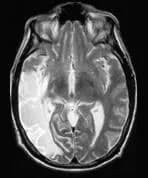

A patient presents with an extensive middle cerebral artery territory infarct.

The MRA demonstrates complete occlusion of the right internal carotid artery (ICA). The perfusion sequence shows prolonged mean transit time in the right frontal area, indicating a delay in the transit time of contrast media as a result of the right ICA stenosis.